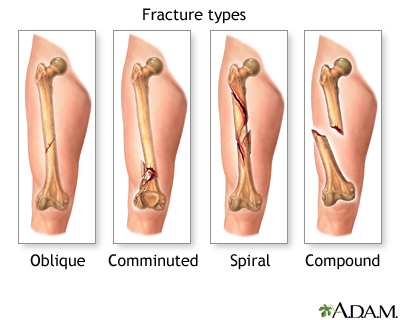

If more pressure is put on a bone than it can stand, it will split or break. A break of any size is called a fracture. If the broken bone punctures the skin, it is called an open fracture (compound fracture).

A stress fracture is a break in the bone that develops because of repeated or prolonged forces against the bone. The repeated stress weakens the bone until it finally breaks.